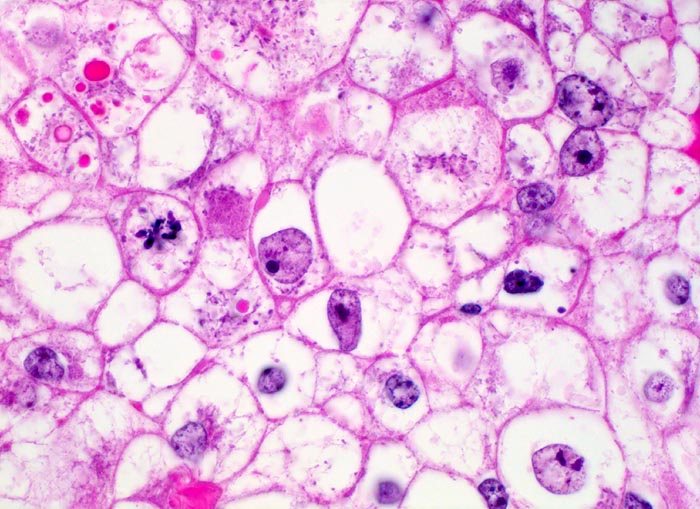

n/ Hellzelliges Nierenzellkarzinom, Urin

Hellzelliges Nierenzellkarzinom, Urin

Typisch für das Nierenzellkarzinom sind relative grosse ein- oder mehrkernige atypische Zellen mit exzentrisch gelegenem Zellkern, plumpen Nukleolen und vakuolisiertem Zytoplasma. Der zytologische Nachweis wird dadurch erschwert, dass die Zellen auf ihrem Weg in die Harnblase degenerieren. Der Kern ist oftmals pyknotisch und das Zytoplasma in Auflösung und eosinophil granuliert. Differentialdiagnostisch muss an Tubulus- oder Sammelrohrepithelien gedacht werden.